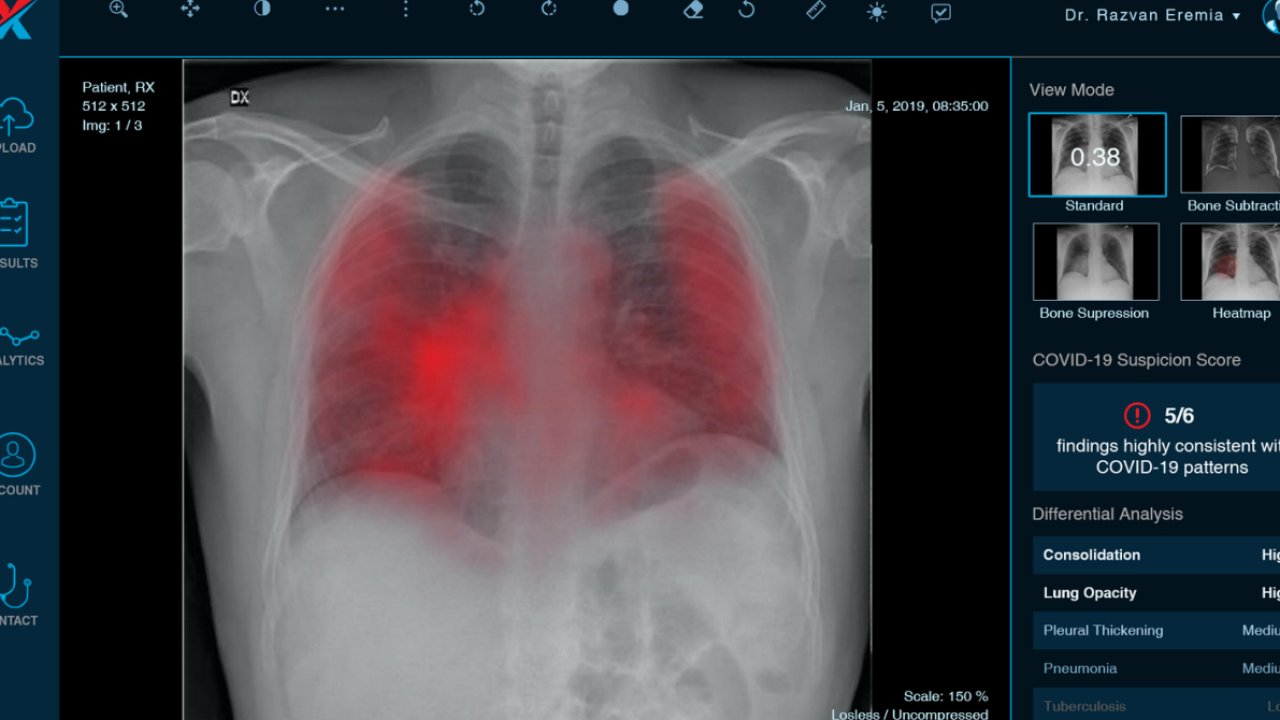

Astfel, timp de 6 luni, spitalele din județ vor beneficia de un soft pentru identificarea a 17 patologii ale aparatului respirator, inclusiv în cazul pacienților cu Covid-19. Soft-ul folosește inteligența artificială și este dezvoltat de startup-ul XVision.

Aplicația dezvoltată de XVision este prima de acest tip din România. Aceasta a fost implementată pentru prima oară în cadrul spitalului Județean de Urgență din Timișoara unde ajută medicii să analizeze până la 200 de radiografii pulmonare/zi, cu 20% mai multe decât în trecut.

La acest moment, aplicația generează date aferente exclusiv zonei toracale folosind ca informație de bază radiografii digitale. În prezent echipa lucrează la dezvoltarea de noi algormitmi ce vor putea interpreta CT-uri toracice și craniene.

XVision folosește algoritmi de inteligență artificială pentru analiza radiografiilor pulmonare. În prezent, programul este implementat în mai multe spitale din țară, ajutând cu succes radiologii în procesul de analiză imagistică.